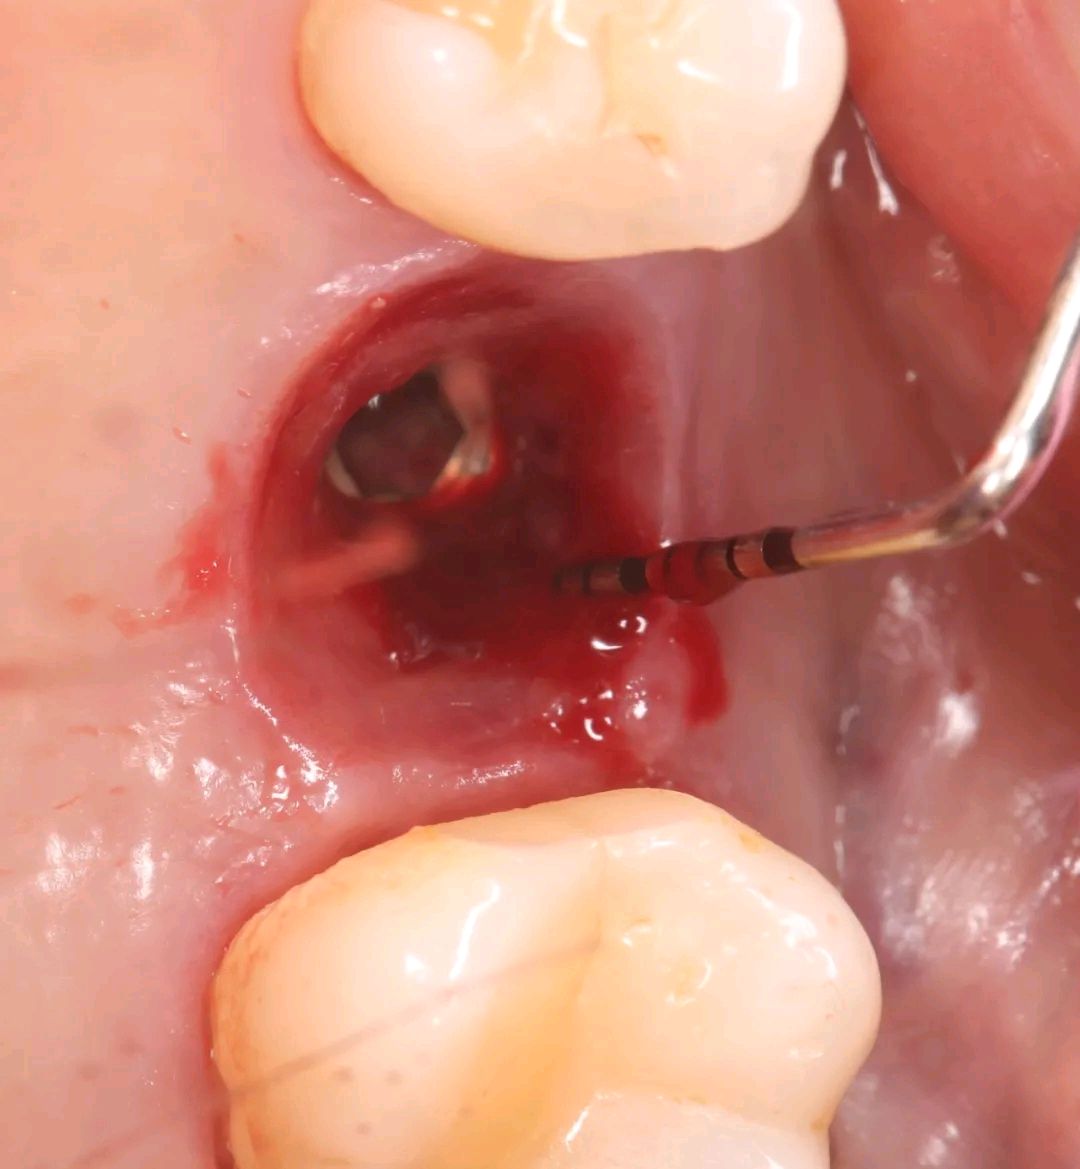

2、16颈部局部清创

3、16翻瓣术彻底清创 暴露的种植体表面及周围